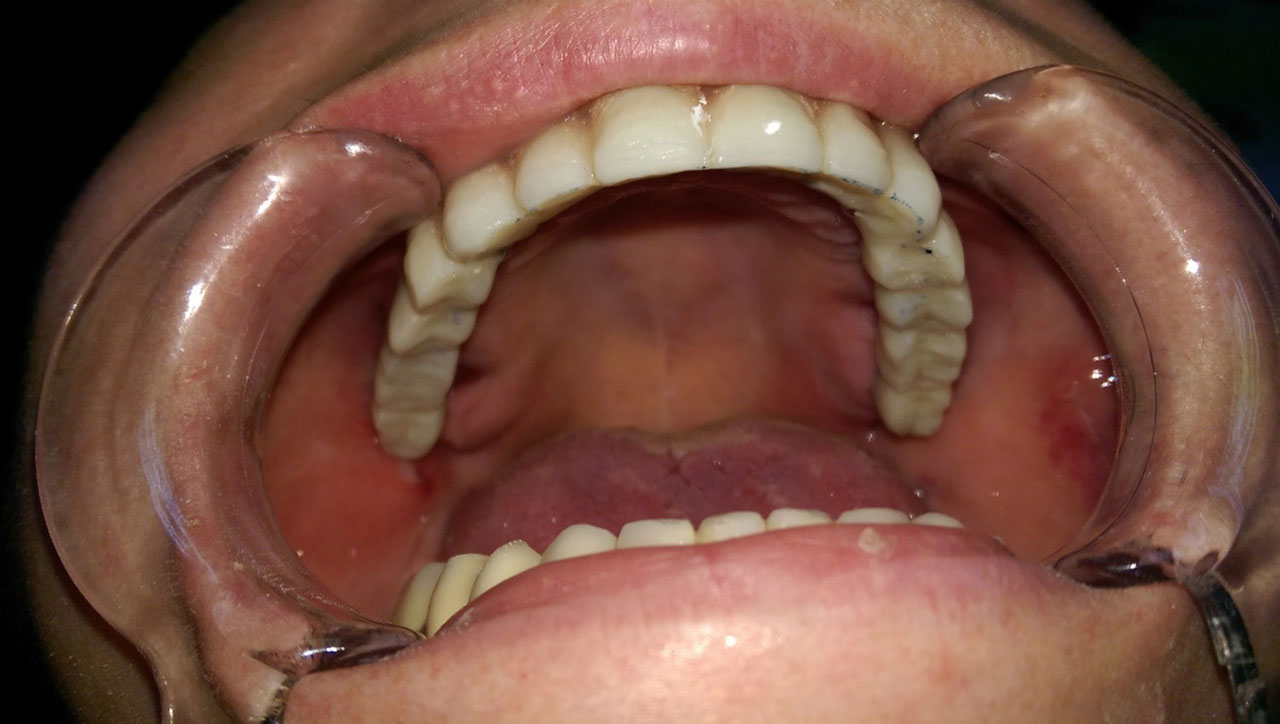

• esettanulmany-43

Így néz ki szájban a hosszútávú ideiglenes híd.(Fém vázzal erősített műanyag híd.)

• esettanulmany-44